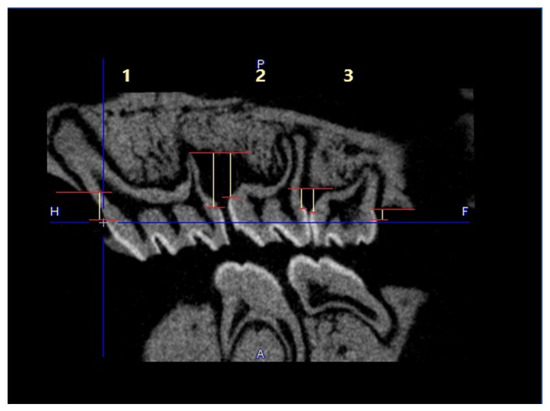

No visible changes were noted in the periodontium. Furthermore, CT scans revealed no alterations in the jawbone area. Due to technical constraints, the experiment was confined to the upper jaw, and alveolar bone loss was quantified using micro-computed tomography (μCT). Measurements were taken from the cemento–enamel junction (CEJ) to the alveolar bone crest (ABC). For each analyzed rat (23 in total), 12 measurements were conducted: three times per molar at two sites (left and right), doubled for statistical replication. The specific distances utilized for statistical analysis are detailed in Figure 8.

Figure 9 presents a representative CT analysis of bone loss in P. gingivalis-infected animals (both minocycline-treated and controls. The beneficial effect of the treatment is clearly visible with regard to bone loss. Comparison of the CEJ-ABC distance shows a significant bone loss in the non-treated animal (A + C, PG), which was remarkably diminished by the treatment (B + D, PG+MIN-T).

This observation has been statistically validated, as shown in Figure 10. Aggregated measurements across all evaluated molars (1st, 2nd, and 3rd upper molars) indicate a significant reduction in bone loss in the treated group PG+MIN-T, with a p-value of <0.0001 compared to the non-treated group (PG). This demonstrates the antibiotic’s effectiveness over 31 days following treatment with the novel formulation.

4.6.1. Micro-Computed Tomography Analysis

To determine bone loss High Resolution Animal Computed Tomography (Micro-CT, MILabs, The Netherlands) was used. All animals were scanned at two time points (before treatment (T0) and on the day of termination of the experiment (TEND)). Imaging was performed at an ultra-focus magnification, 50 kV source voltage, and 0.21 mA current. Three-dimensional images were obtained using the PMODE software (vers. 4.3; Fällanden, Switzerland). To assess the alveolar bone loss, a linear distance from CEJ to ABC of each tooth of the lower and upper jaw was measured. Each measurement was performed three times, and the data are presented as the mean ± standard deviation (SD). The results are presented as the distance after subtracting the basal measurement (T0) from the measurement obtained at the endpoint of the procedure (TEND).